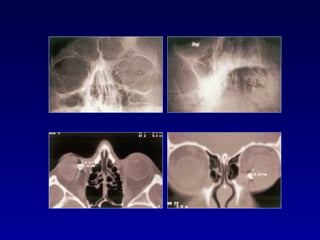

5. FRACTURA ORBITARIA:

Fracturas directas: Se palpa un escalón en el reborde

Fracturas indirectas por estallamiento: Suelen

ser producidas por pequeñas pelotas, balines etc.

Sospechar cuando se observa dificultad en la mirada

vertical y enoftalmos. Verificar la conservación de la

sensiblidad de la mejilla y del labio superior del

paciente para descartar lesiones del nervio

infraorbitario.

Tratamiento: antibióticos orales, descongestivos nasales,

aplicación de hielo y esteroides orales.

Requieren tratamiento quirúrgico.